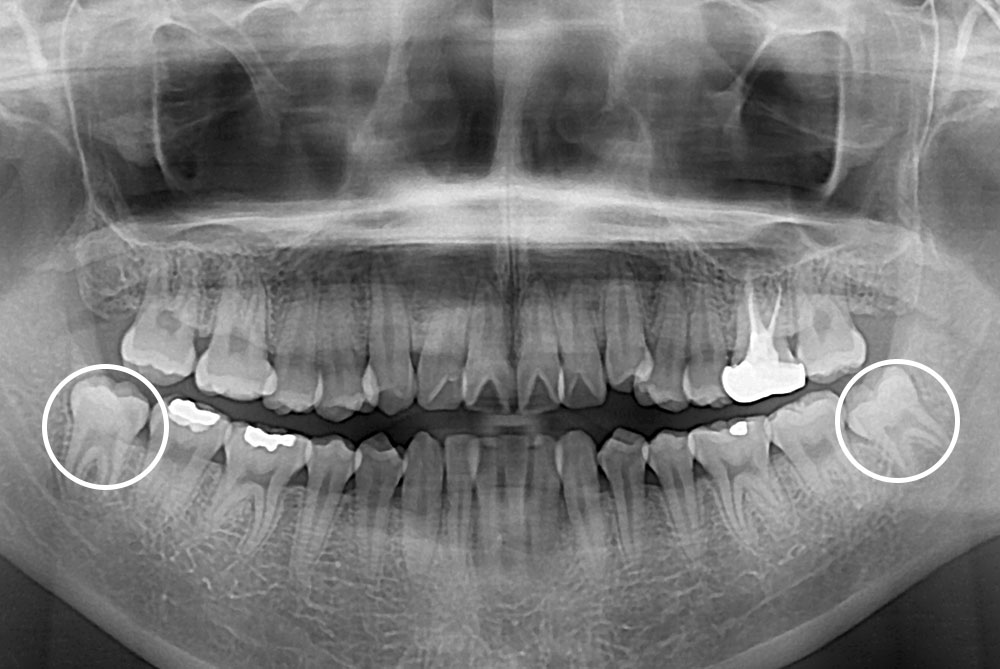

[사랑니] 매복 사랑니 발치

치료전 : 2017-12-14